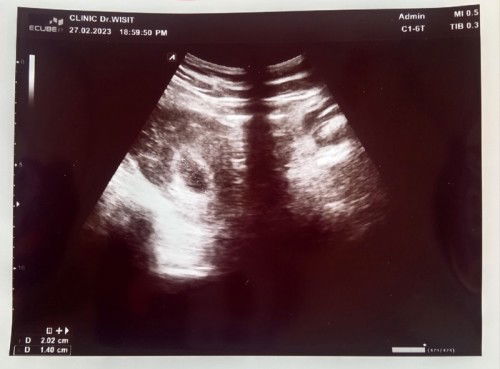

จากภาวะแท้งคุกคามมีเลือดไหลเหมือนประจำเดือนมาทุกวันจนครบอาทิตย์ แม่ก็ได้ไปหาหมอเฉพาะทางมาเมื่อวานซืน ซาวด์แล้วยังเจอถุงตั้งครรภ์อยู่ แต่ยังไม่เจอตัวเด็ก ถุงตั้งครรภ์ตอนนี้2เซนแล้ว อายุครรภ์หมอบอกน่าจะประมาณ6สัปดาห์ อีก2สัปดาห์นัดซาวด์อีกทีว่าถุงตั้งครรถ์ขยายตัวขึ้นไหม ถ้าไม่ขยายตัวขึ้นถุงตั้งครรถ์ก็อาจจะฝ่อ อันตรายต่อแม่และเด็ก แม่ๆท่านใดมีประสบการณ์แบบนี้บ้างค่ะ ตอนนี้แม่เครียดมากเลย กลัวจะแท้งสมบูรณ์แล้วหลุดออกมาเอง เพราะเลือดไม่หยุดไหลเลย #คุณแม่ๆช่วยแนะนำหน่อยค่ะ